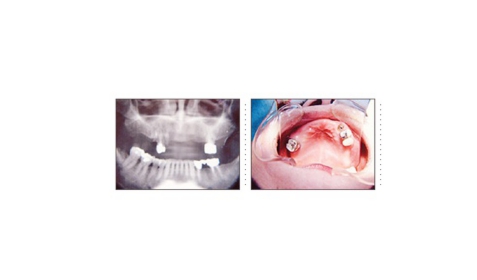

症例10

64才 男性

地元の有名寿司屋さんの店主の方(インプラント患者さん)からの御紹介です。

上顎の義歯をインプラントに変えたいとの希望で来院されました。

このケースはまずはじめに局部床義歯を作り直します。インプラント部と義歯床が接触するのを避ける為、部分的に床を削れるようにクラスプ、補強線の位置を決定します。顎骨の質・量ともに十分で、インプラント埋入は簡単です。右側4本のインプラント埋入は8分で終わりました。3ヶ月後には残存歯全て抜歯し、フルブリッジタイプの仮歯をセット。仮歯の段階で十分に咬合のチェックをし、3~4ヶ月抜歯窩の治癒を待ち最終的にフルブリッジへと移行します。